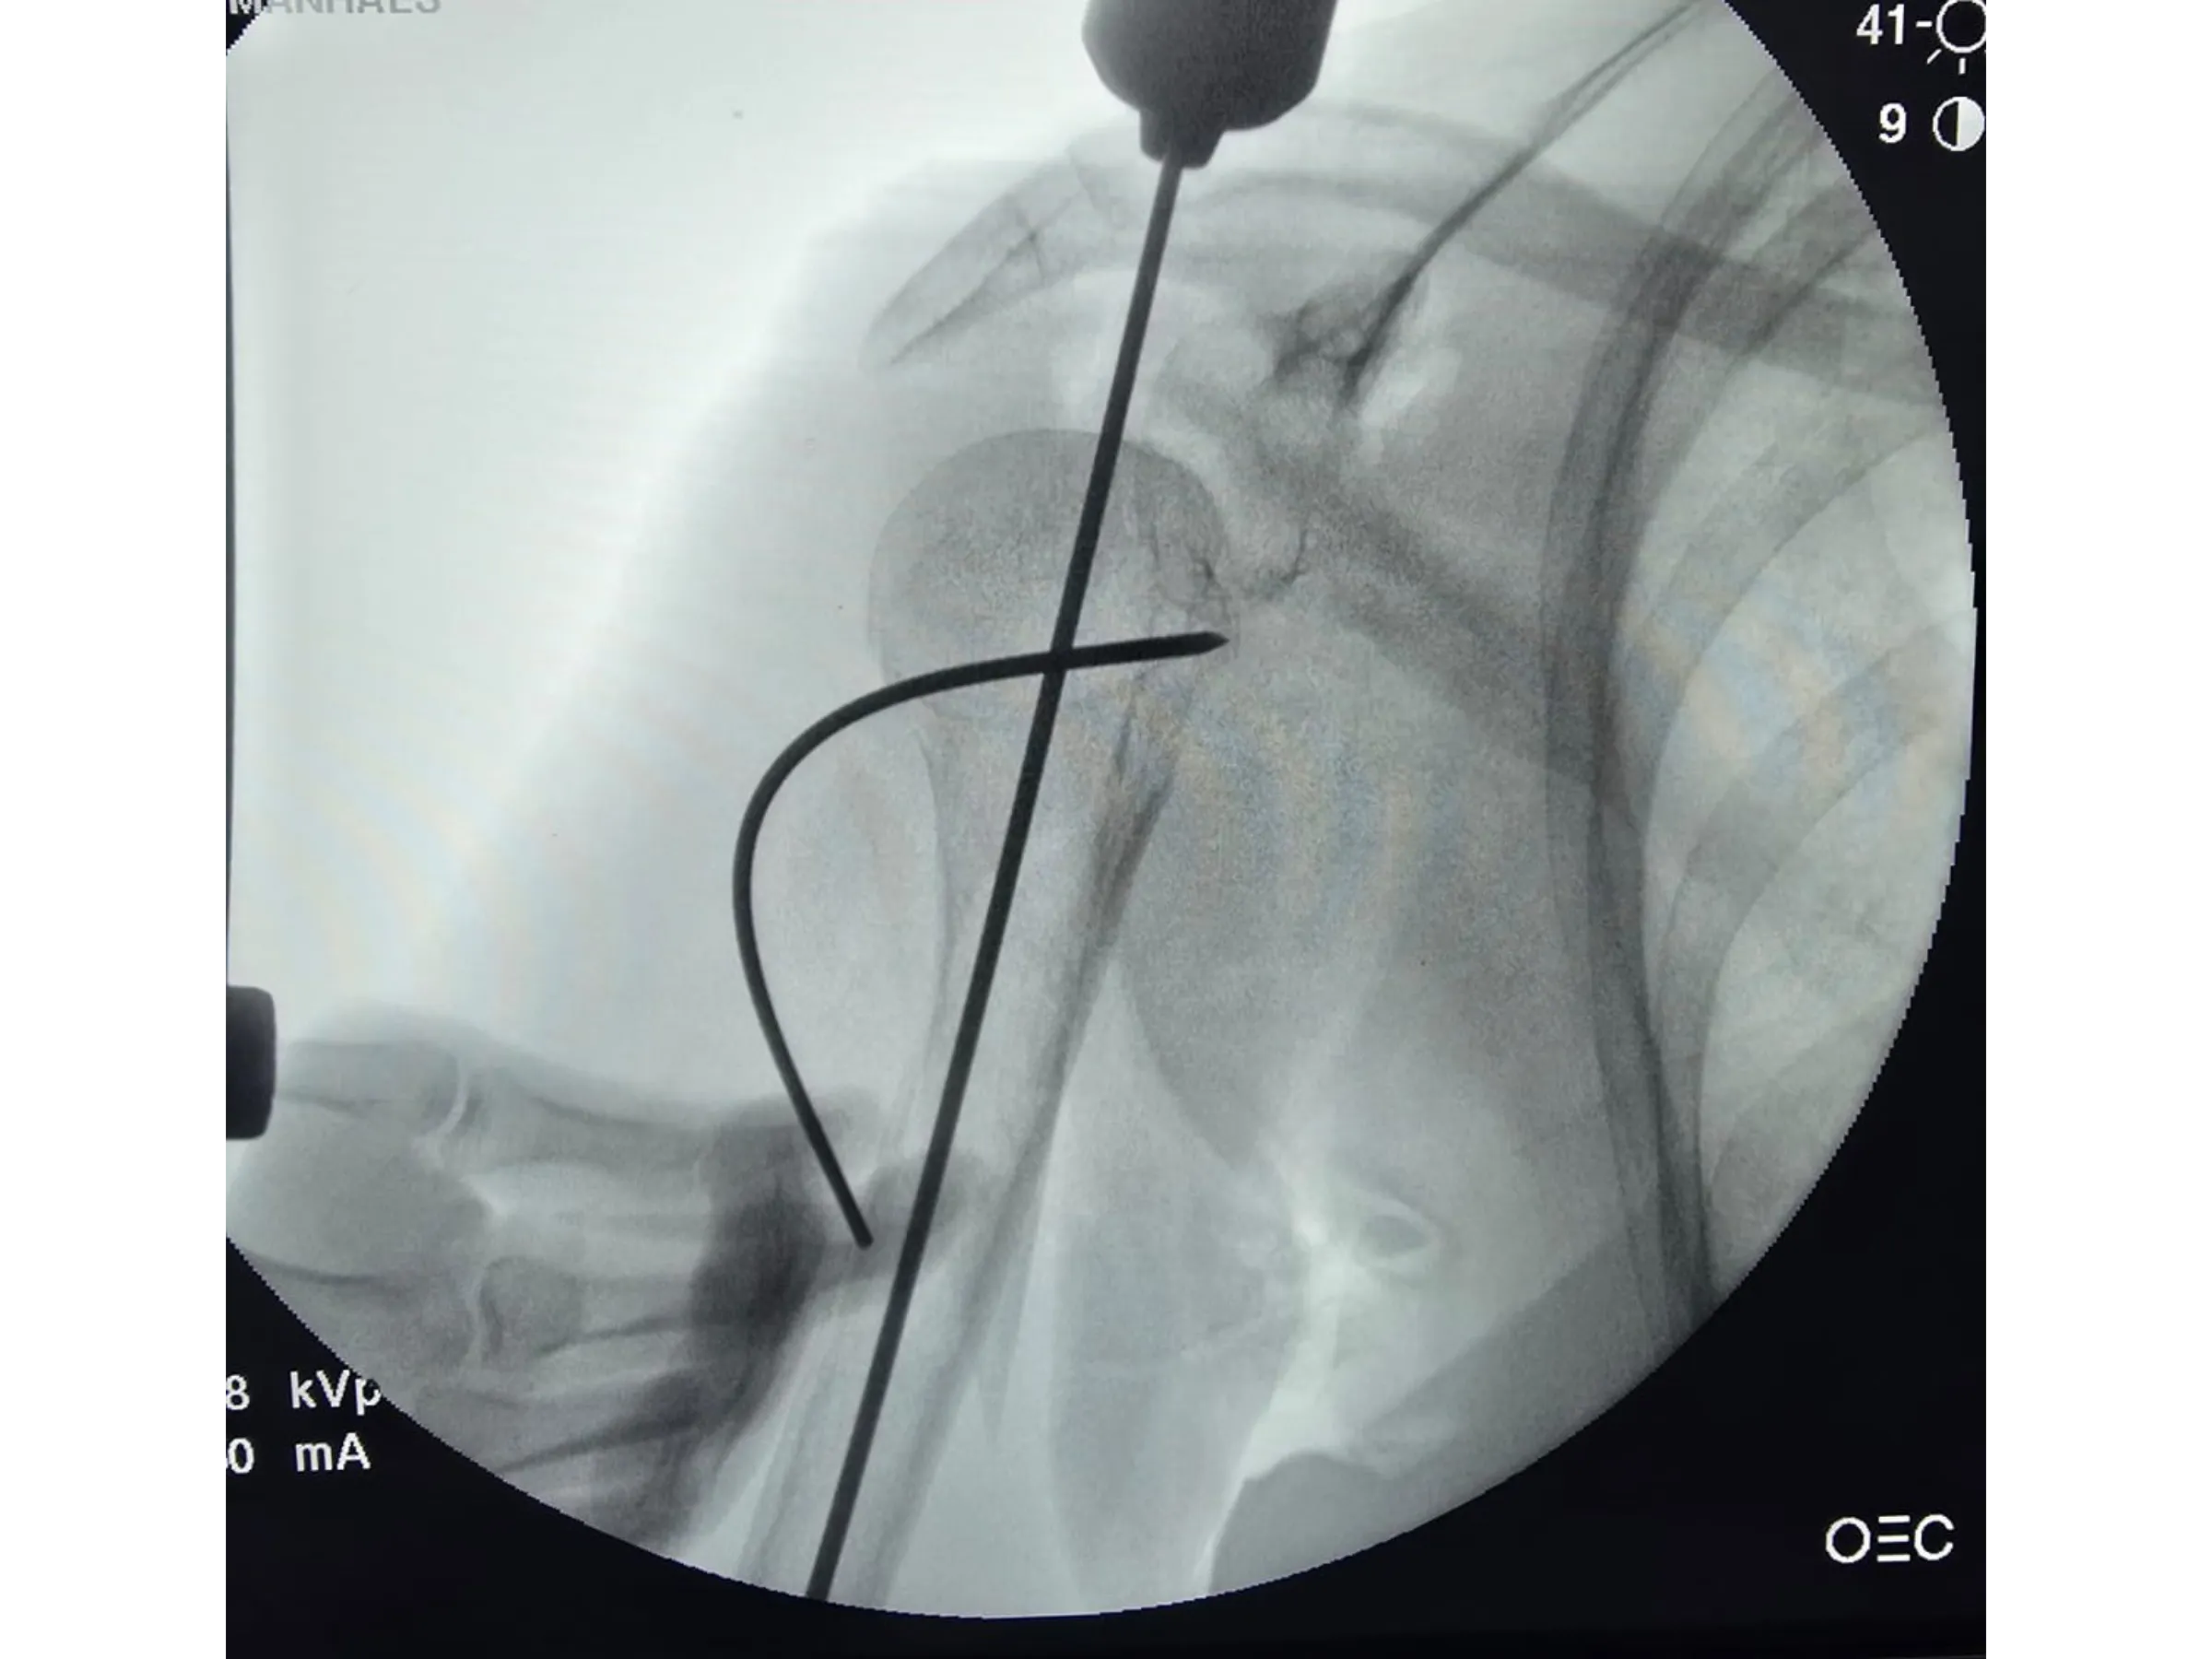

- Kirschner wire joystick-type manipulation.

- Joystick for Humeral Head Alignment: Safe manipulation for correcting the angle and centering of the entry point.

- Rigorous Fluoroscopic Control: Anteroposterior and lateral images to ensure parallelism and precision of the implants.